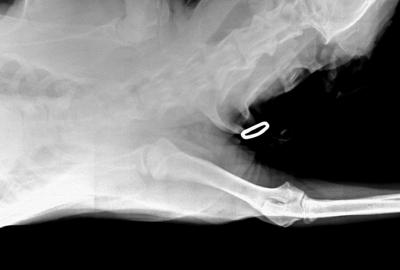

RTG Dysplazie kyčelního kloubu (DKK)